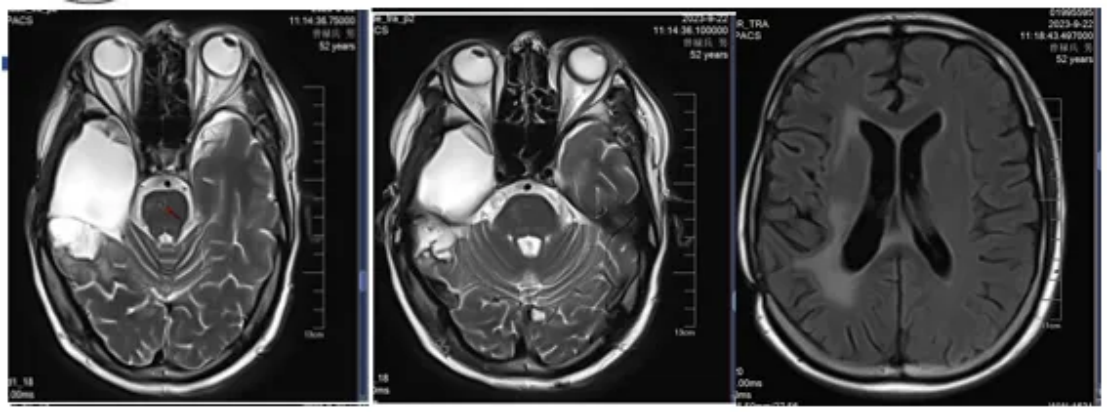

2023-9-22脑部MRI随访复查:右侧颞叶胶质瘤术后;右侧基底节区后部点状异常信号,较前(2023-06-15)相仿,建议定期复查;右侧大脑脚华勒氏变性;桥脑小片状异常信号,较前新发,软化灶伴出血?转移待排;右侧胼胝体压部及桥脑急性腔梗,较前新发,随诊复查;右侧侧脑室周围缺血灶;右侧基底节区陈旧性腔梗灶;两侧筛窦炎(图7)。

图7 颅脑MRI图像